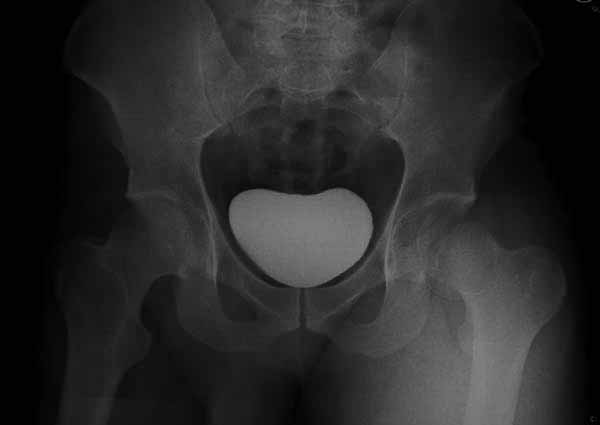

В молодом возрасте (23 лет) даже самый продвинутый эндопротез не заменит собственную головку, и здесь рекомендуется органосохраняющая операция.

При сопутствующем переломе головки с ацетабулум, тогда артротомия из того доступа, который позволит фиксировать перелом впадины и фиксировать головку шурупами. На сегодня Headless Screw Synthes имеет преимущества перед другими, но при отстутствии их можно сделать обычными 3.5 мм., только головку надо утопить. При изолированном переломе доступ через trochanteric flip approach, который позволяет вывихнуть головку из ацетабулума и свободно работать без риска АВН. В вашем случае можно из переднего Smith Petersen доступа, потому что осколок спереди.